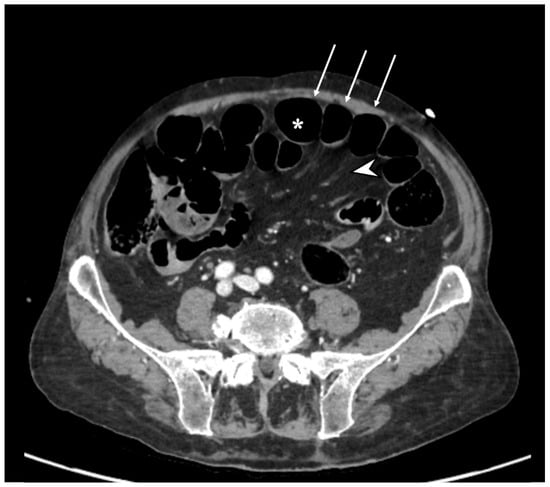

2. Case Report